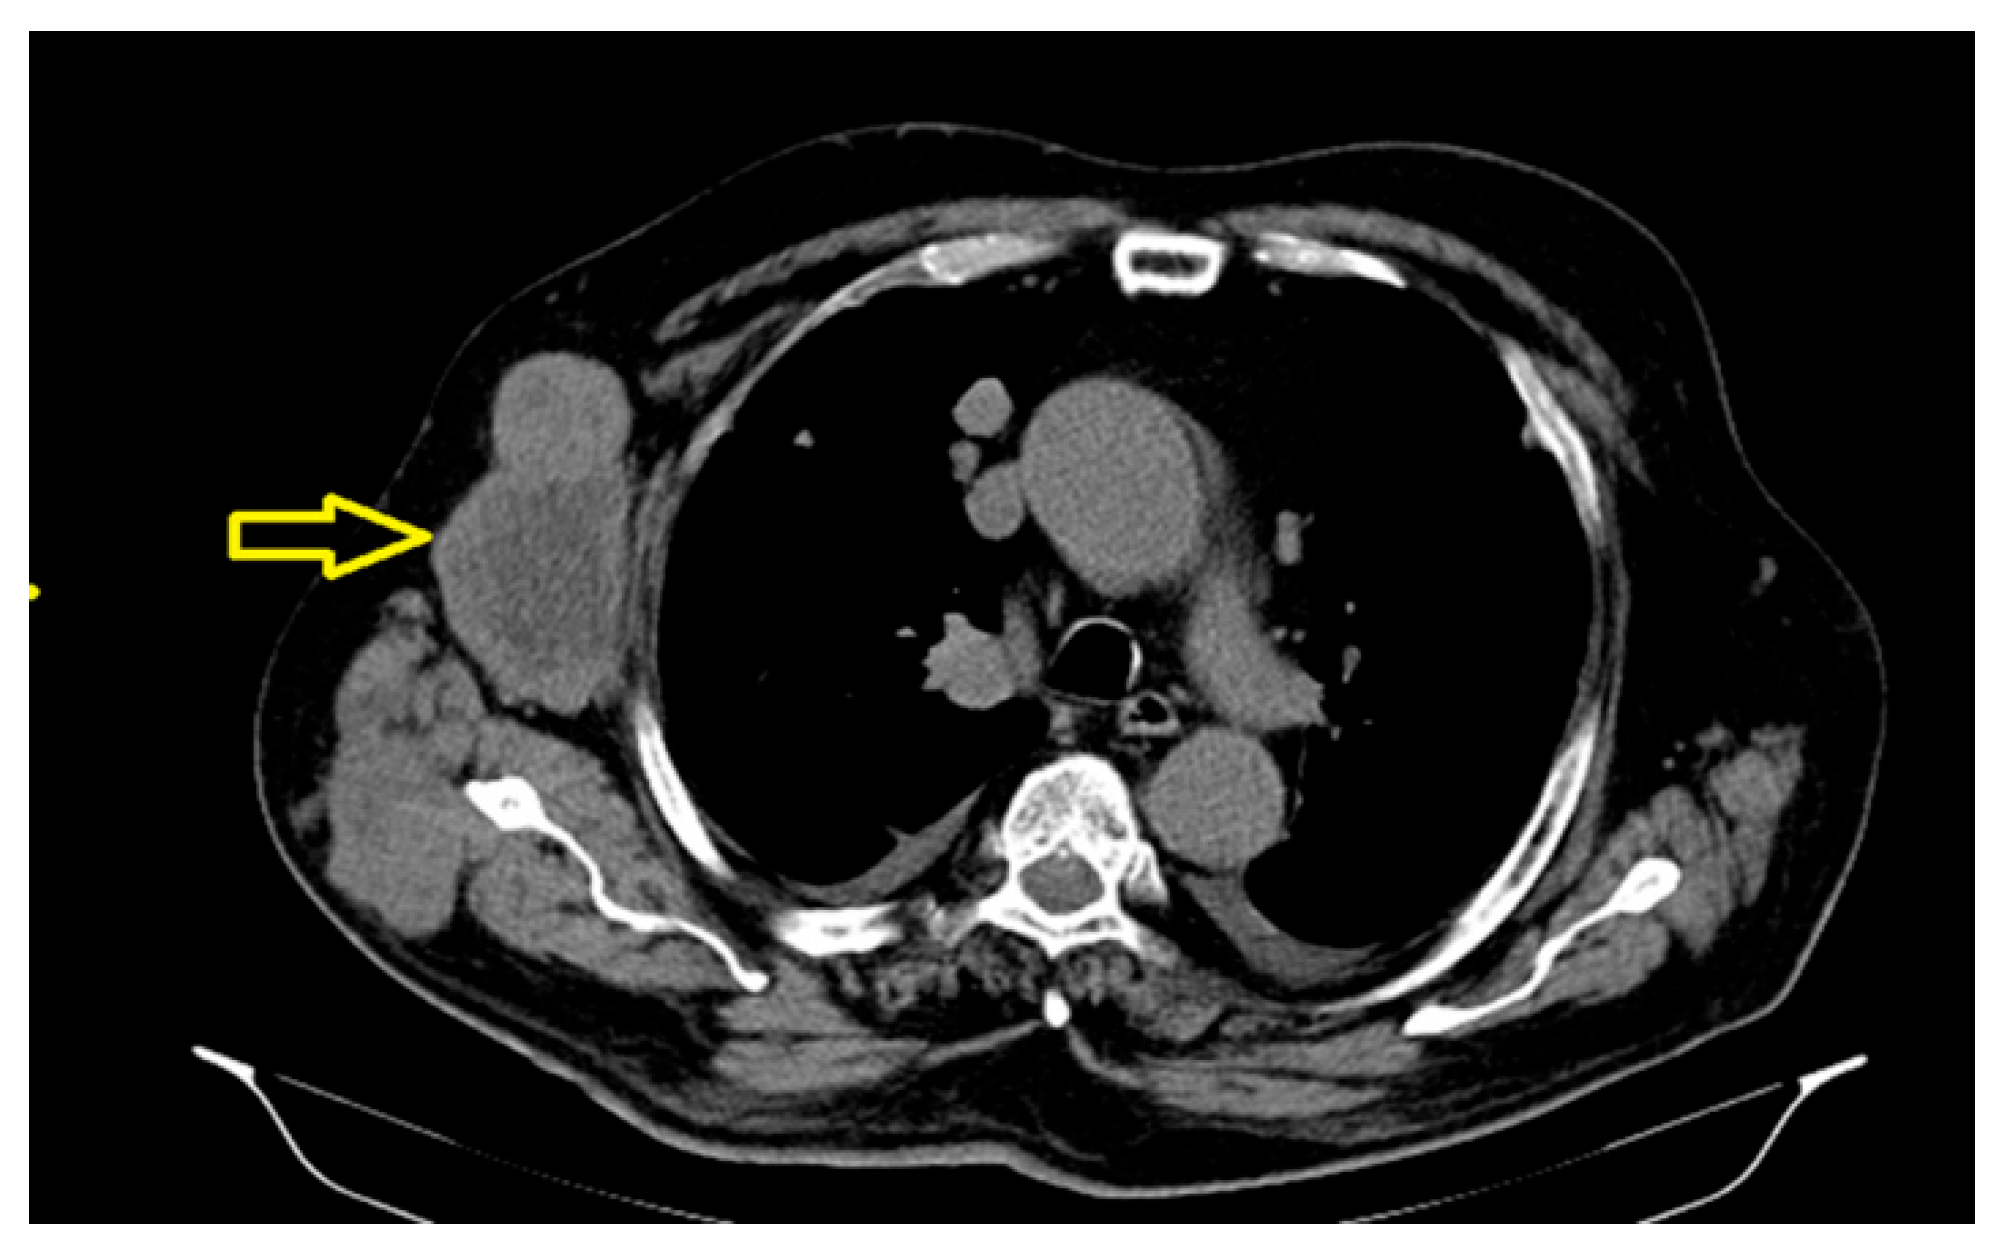

The significant dimensional progression of the right axillary tumor adenomegaly, currently associated with extensive central necrosis, was also determined (Figure 4), along with an osteocondensation -focused lesion centered on the left pubic branch with a suspicious aspect for secondary determination.

Figure 4. The important dimensional progression of the right axillary tumor adenomegaly, currently associated with extensive central necrosis.